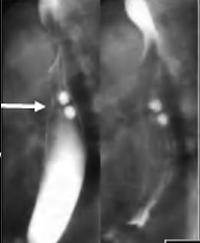

Mega oesophage : image radiologique

TDM fenetre parenchymateuse en coupe axiale |

Image Achalasia de oesophage en

coupe TDM sagitale |

Meme cas en coupe TDM frontale ( coronale

) . |